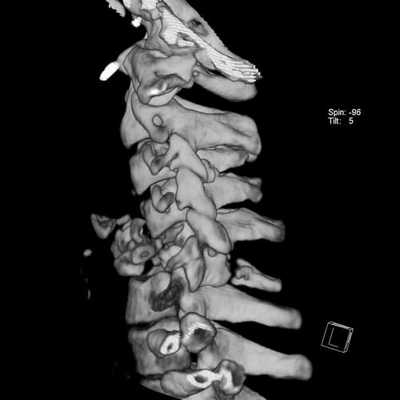

Шейный отдел позвоночника отличается от других большой физиологической подвижностью и минимальной осевой нагрузкой. Ширина позвоночного канала в шейном отделе также существенно меньше чем в нижележащих. В то же время, в шейном отделе рано проявляется спондилез - комплекс дегенеративных изменений в виде обызвествления связок, краевого остеофитоза, артроза дугоотростчатых суставов и унко-вертебральных сочленений. Грыжи дисков в шейном отделе редко бывают большие и медиальные. Хотя при таких грыжах может быть смещение и даже сдавление спинного мозга, они долго протекают бессимптомно. Большинство грыж парамедиальные, которые сопровождаются остеофитами, формируя “твердые” грыжи. При МРТ шейного отдела позвоночника видно, что они часто двухсторонние, сдавливают передний корешок, вызывая типичную корешковую боль вдоль руки. Особенно коварны боковые (фораминальные) грыжи, так как они не всегда отчетливо видны при МРТ шейного отдела позвоночника. Особенно надо отметить, что в шейном отделе позвоночника слабо развита эпидуральная жировая клетчатка, что усложняет визуализацию грыж в аксиальной плоскости на Т2-взвешенных МРТ. Градиентные аксиальные МРТ шейного отдела позвоночника лучше показывают корешок и его сдавление. Сдавление корешка на поперечных МРТ шейного отдела видно как его смещение, отек, стирание четкости границ и, иногда, расширение эпидуральной вены. Спондилез и грыжи дисков приводят к стенозу (сужению) позвоночного канала, нарушения кровообращения по эпидуральным венам и артериям спинного мозга, вызывая его локальный отек и изменения по типу миеломаляции. При МРТ позвоночника в таких случаях виден светлый участок на Т2-взвешенных МРТ. Состояние может быть обратимым, если вовремя оперирована грыжа или проведена сосудистая терапия. Тогда на МРТ нейного отдела позвоночника в сагиттальной плоскости высокий сигнал на Т2-взвешенных МРТ изображениях уменьшается или совсем исчезает. При МРТ в СПб этому симптому мы придаем особое значение, так как он связан с миелопатическим синдромом и говорит о необходимости неотложных лечебных мероприятий.